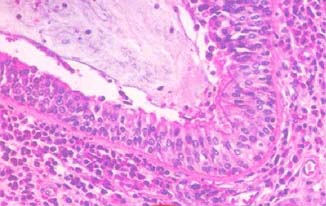

胃液吸入气道可引起哮喘发作。胃食管反流症状的发生率为45%~60%;胃烧灼热感症状约77%,反酸感觉者约55%。任何可致食管下段括约肌张力降低的因素均可加重反流。

目前认为胃食管反流引起哮喘的机制可能主要是食管下段括约肌张力降低引致。

1.胃液成分刺激食管迷走神经的传入神经,经气道的迷走神经传出,导致支气管痉挛。哮喘早期吸入抗胆碱能制剂比吸入拟交感神经药物的反应更佳,可说明这一观点。

2.胃液反流至气道,可致使支气管痉挛,这是因胃液中酸性成分的刺激,引起气道阻力增高。在激发试验中,若酸性液体流入气道,那么支气管痉挛作用将增加2倍以上。应用抗酸药物后支气管痉挛症状可改善。

3.胃液反流使支气管反应性增高,增强了哮喘患者对各种触发因素的敏感性。